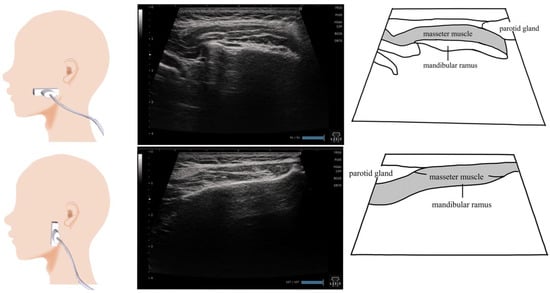

7. Masseter Muscle (Figure 6)